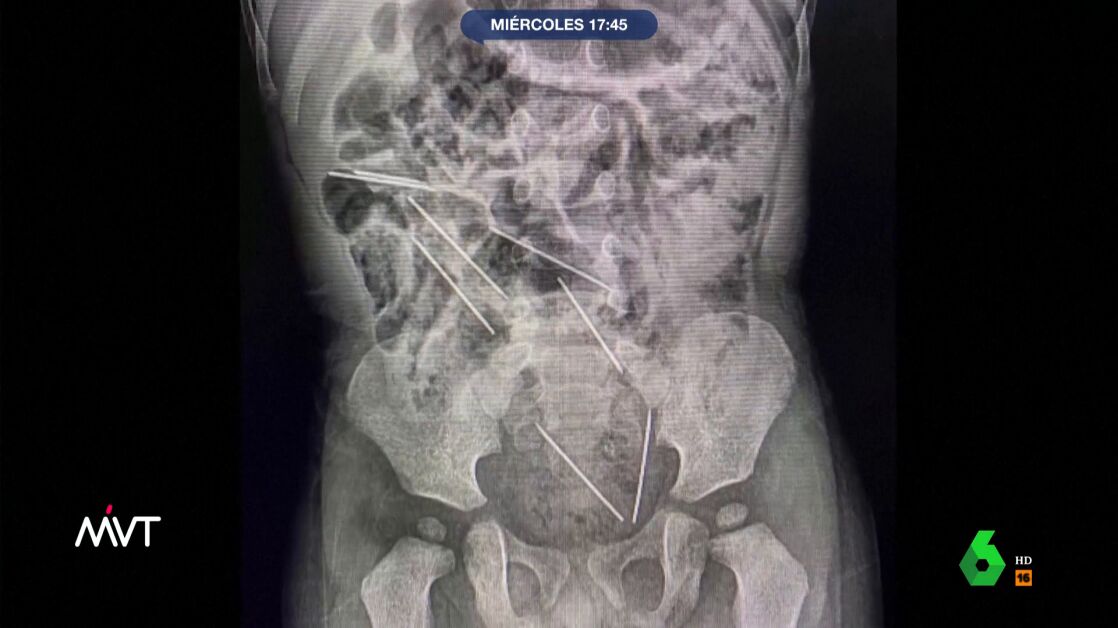

Un niño de dos años se traga ocho agujas para vacas en Perú y es intervenido de urgencia

El niño ingirió las ocho inyecciones mientras jugaba en la finca donde trabajaba su madre. El pequeño fue operado de urgencia y se recupera rápidamente.

Un pequeño de dos años se tragó ocho inyecciones para vacas en Perú. Los médicos lograron actuar con rapidez y sacárselas del estómago y del tracto intestinal a través de una operación de urgencia.